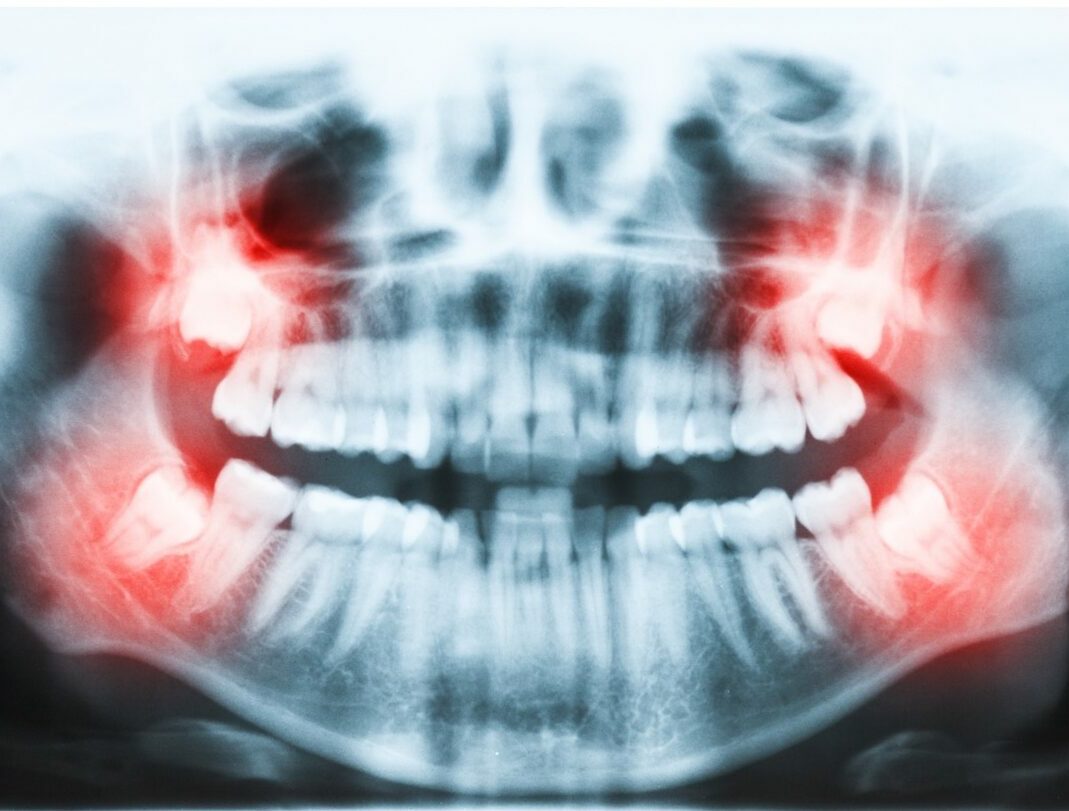

“Wisdom teeth can cause trouble silently. You won’t feel pain, but X-rays show cysts, wrong angulation, or decay forming on the tooth in front. By the time you feel it, it’s often too late.”

Examples of silent but serious issues:

- Cysts that hollow out the jaw

- Bone loss around the second molar

- Cavities caused by an impacted tooth

- Nerve compression

- Jaw fracture risk